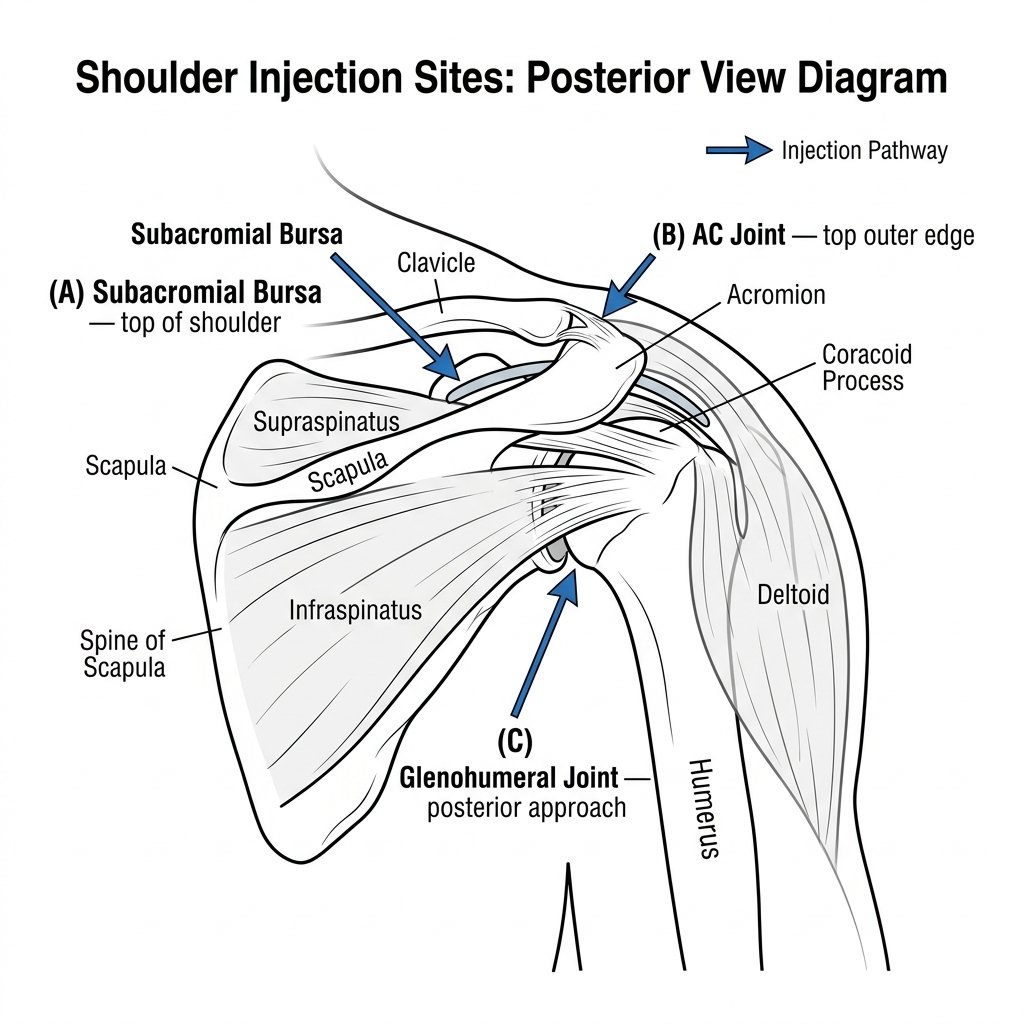

1 Essential Ultrasound Guided Shoulder Injection London Guide

Ultrasound guided shoulder injection London — performed by a specialist musculoskeletal radiologist — is one of the most effective, fastest-acting...